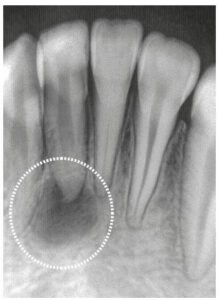

Come si vede un granuloma?

Il granuloma periapicale viene diagnosticato dal dentista tramite la radiografia dentale (chiamata ortopanoramica o ortopantomografia). Si può notare una radiotrasparenza rotonda in corrispondenza dell’apice di un dente.